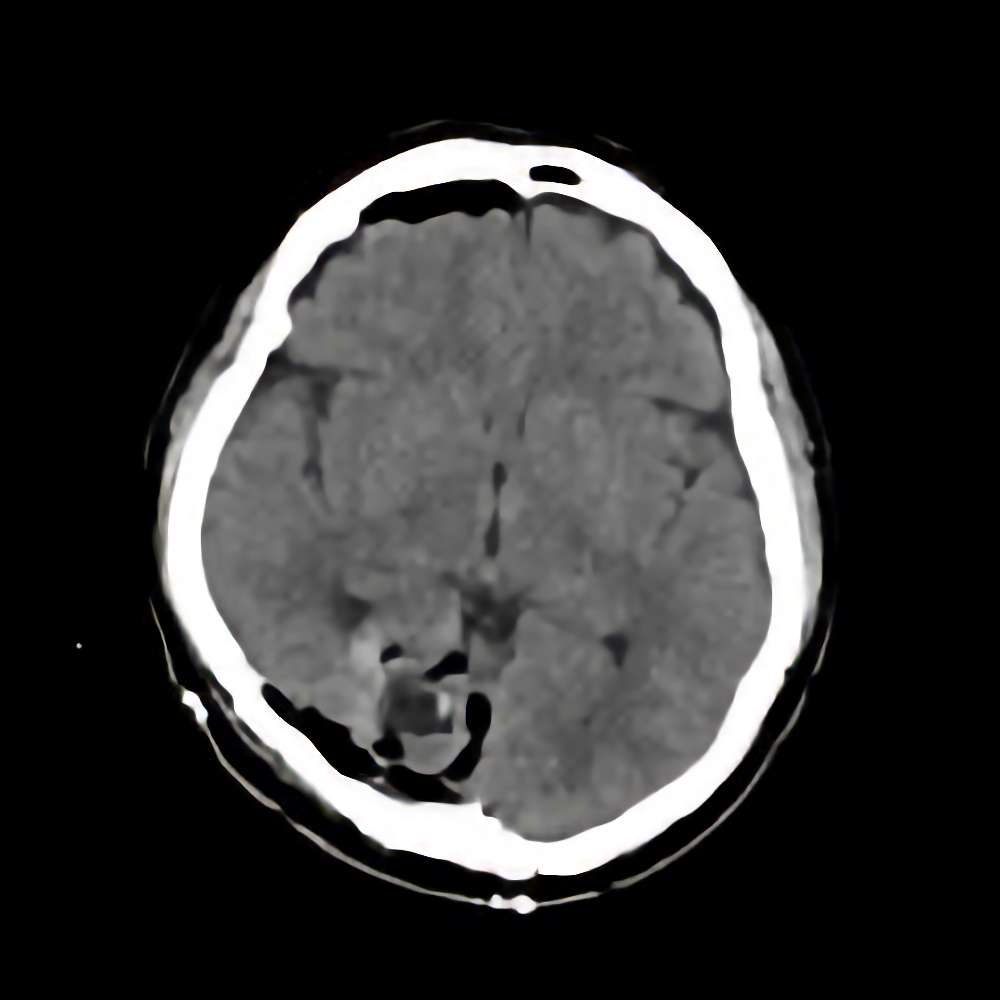

脳腫瘍 手術実績

症例 '15年7月

No.

※ 画像をクリックすると拡大表示します。症例No.は平成29年から起算しています。

年_番号

手術年月

患者年齢

’15_103

'15年7月

50代

病名

術式

備考

脳腫瘍

断層撮影

手術前

1

手術前2

手術後